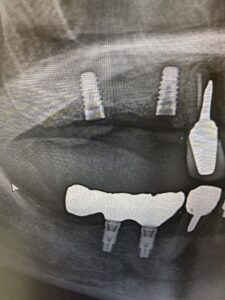

インプラント症例がありましたのでご紹介。

40代男性。当院で3回目のインプラント。

右上に2本埋入しました。